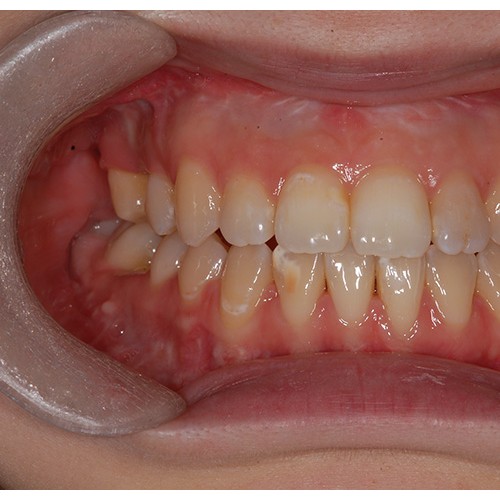

CHUNCHU'S ORTHODONTIC CLINIC# BEFORE_AFTER

춘추치과교정과를 방문해주신 분들의전후 사진을 확인해보세요.